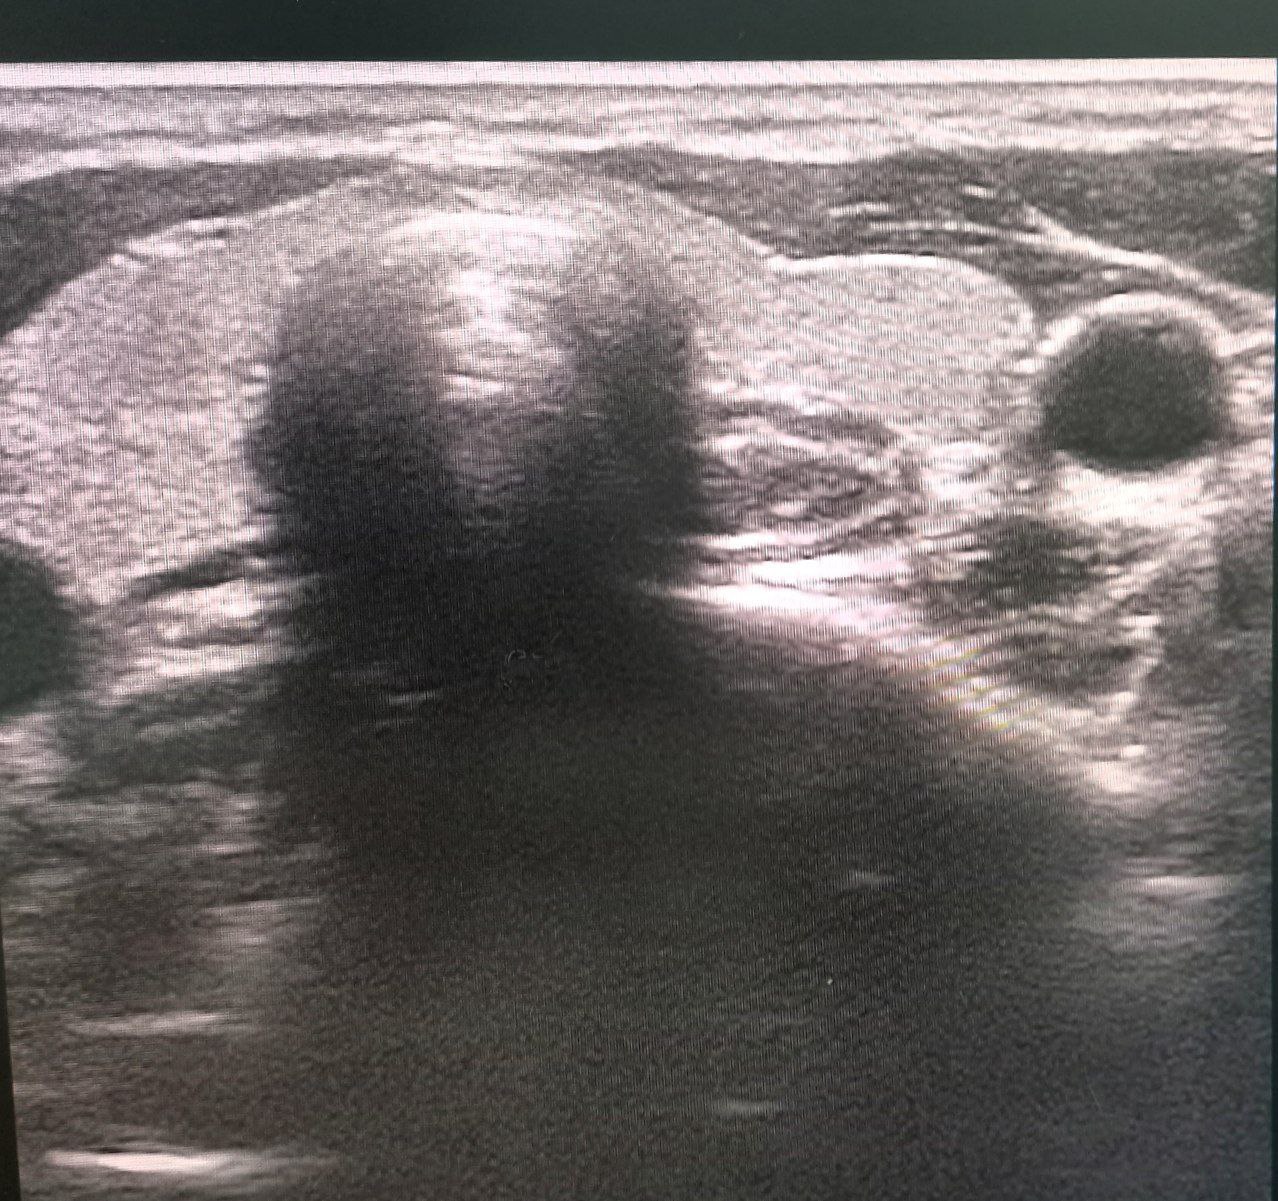

Склеротерапию кисты или узла щитовидной железы делают под непрерывным контролем ультразвука, обеспечивающего высокую точность введения вещества. Отсутствует риск повреждения окружающих структур — сосудов, нервов и паращитовидных желез.

Под постоянным контролем УЗИ, позволяющего точно визуализировать иглу и узел, врач тончайшей иглой медленно вводит препарат. Вещество вызывает локальное обезвоживание и коагуляцию белков клеток узла, приводя к его разрушению. После инъекции игла извлекается, а на место укола накладывают повязку.

• ультразвуковое исследование щитовидной железы с допплерографией;